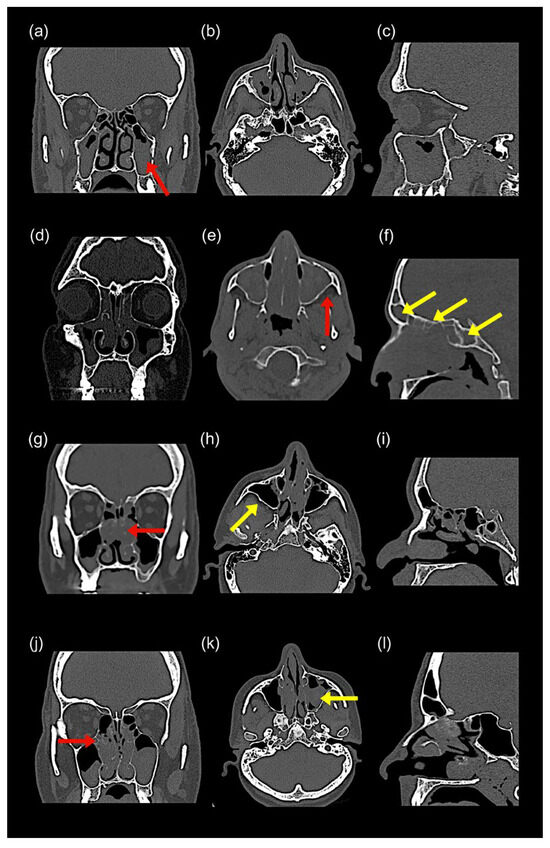

16 pages, 1722 KB

A Clinically Relevant Classification and Staging System for Chronic Rhinosinusitis with Nasal Polyposis: A Cross-Sectional Study

Diagnostics 2025, 15(24), 3197; https://doi.org/10.3390/diagnostics15243197 - 14 Dec 2025

Background/Objectives: Tissue eosinophilia plays a central role in chronic rhinosinusitis with nasal polyposis (CRSwNP), yet the spectrum of disease, particularly central compartment atopic disease (CCAD), remains underexplored. This study aimed to classify CRSwNP into three distinct phenotypes, eosinophilic CRSwNP (ECRSwNP), non-eosinophilic CRSwNP (NECRSwNP), [...] Read more.

Background/Objectives: Tissue eosinophilia plays a central role in chronic rhinosinusitis with nasal polyposis (CRSwNP), yet the spectrum of disease, particularly central compartment atopic disease (CCAD), remains underexplored. This study aimed to classify CRSwNP into three distinct phenotypes, eosinophilic CRSwNP (ECRSwNP), non-eosinophilic CRSwNP (NECRSwNP), and CCAD, based on radiologic and endoscopic features. It also proposes a novel severity-based staging system to guide clinical decision-making. Methods: A cross-sectional observational study was conducted in a single private clinic between January 2019 and August 2025. Patients were assessed using clinical history, paranasal sinus computed tomography (CT), and intranasal endoscopy. Key variables included symptom clusters, comorbidities, hematologic and atopy profiles, radiologic and endoscopic findings, histopathology, and pre-treatment SNOT-22 scores. Results: A total of 2060 patients (mean age: 29.8 ± 11 years; 51.8% male) were included. Asthma was the most frequent comorbidity (23.5%). Classification into ECRSwNP, NECRSwNP, and CCAD was achieved using integrated clinical, radiologic, and histopathologic criteria. Conclusions: This study presents a phenotype- and severity-based classification system for CRSwNP that incorporates endoscopic and radiologic features. This framework may enhance diagnostic accuracy and enable more tailored therapeutic strategies. Full article

Show Figures

Figure 1